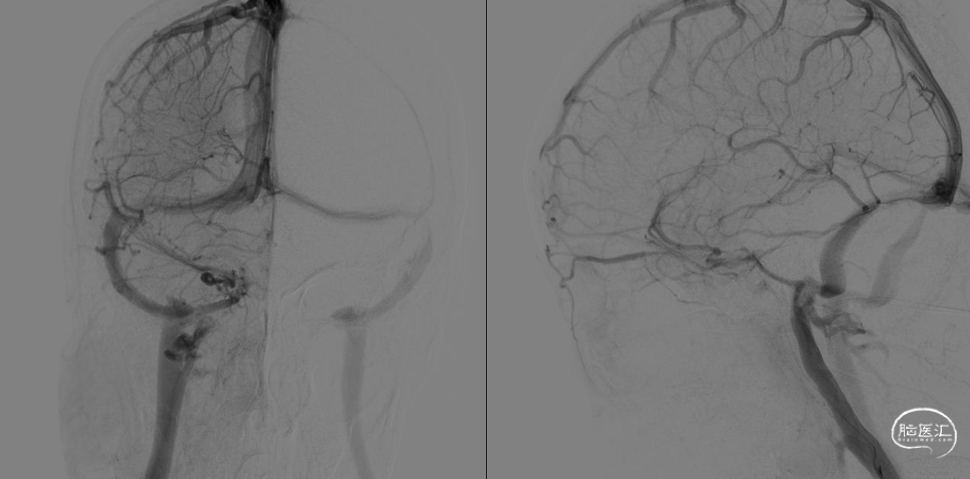

术前DSA:双侧横窦乙状窦交界处重度狭窄。

首先,建立右侧桡动脉通路,进行常规全脑血管造影,明确双侧横窦乙状窦交界区狭窄,排除动静脉瘘。再建立右侧股静脉通路,5F 125 造影导管与6F长鞘组成同轴系统,将长鞘置于右侧颈内静脉远心端。泥鳅导丝引导下将造影导管置于右侧横窦近窦汇处,通过造影导管行静脉窦测压,狭窄远端压力22mmHg,狭窄近端压力21mmHg,跨狭窄段压力差为1mmHg,故放弃右侧静脉窦支架植入术。

再利用同轴技术将6F 长鞘置于左侧颈内静脉远心端。尝试通过泥鳅导丝将造影导管置于左侧横窦失败,撤出造影导管,更换XT-27微导管,在Transend Floppy 300微导丝引导下顺利到达窦汇处。通过微导管进行静脉窦测压,狭窄远端压力26mmHg,狭窄近端压力18mmHg,跨狭窄段压力差为8mmHg,故决定行左侧静脉窦支架植入术。